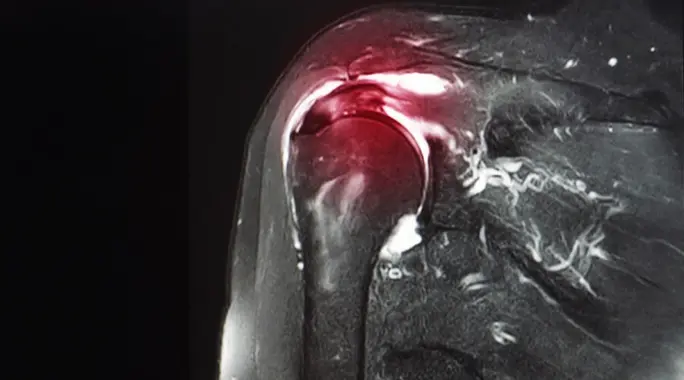

ما هو تمزق أربطة الكتف؟

تمزق أربطة الكتف هو إصابة تصيب الأنسجة الرخوة التي تدعم مفصل الكتف وتمنحه استقراره وقدرته على الحركة. الأربطة هي أشرطة قوية من النسيج الضام تربط العظام ببعضها البعض، بينما الأوتار تربط العضلات بالعظام. يمكن أن يكون التمزق جزئيًا، أو قد يقطع الرباط أو الوتر بالكامل، مما يؤثر بشكل كبير على وظيفة الكتف.

تتراوح شدة التمزق من بسيط إلى حاد، وبمرور الوقت، يمكن أن تتفاقم التمزقات الصغيرة لتصبح أكبر، مما يستدعي تدخلًا علاجيًا.